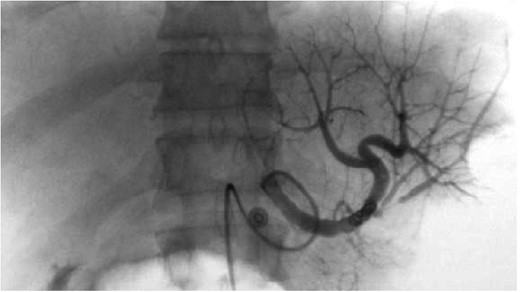

Splenic artery angiogram after placement of embolization coil showing patency of flow, no active extravasation.

Two general methods for TSAE of splenic injuries have been advocated. One option is coil embolization of the proximal splenic artery, which decreases arterial pressure in the spleen but allows continued perfusion through collateral arteries. The other method is superselective embolization of the bleeding arterial branch. To arrest the hemorrhage from splenic injury and to minimize infarct due to embolization, it is important to select appropriate method of TSAE on the basis of the features of arterial injuries [4–6]. Our patient was managed with coil embolization of the proximal splenic artery and subsequently maintained partial perfusion of splenic tissue.